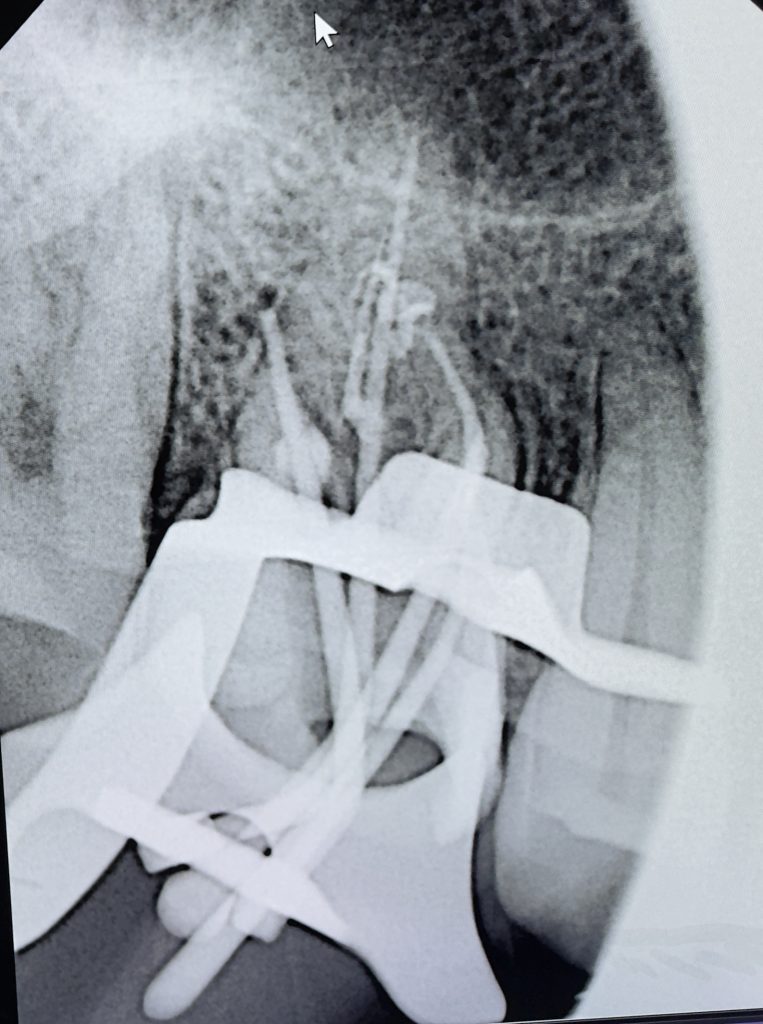

The pulpal floor was scouted with DG-16 and C+ files #6–10. The MB2 was negotiated and confirmed with apex locator. Shaping was performed using rotary NiTi files with 5.25 % NaOCl and 17 % EDTA, both activated ultrasonically for maximum debridement (Fig 4).

Fig 4: MB2 negotiation and working-length verification.